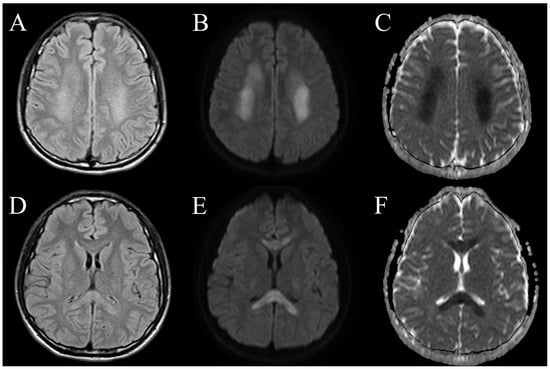

| Radiological features | T2 FLAIR: diffuse, multifocal hyperintensities in the supratentorial and infratentorial white matter, but may also involve gray matter and/or the spinal cord. DWI: increased diffusivity ADC: decreased values in the acute stage; increased values in the subacute stage [16]. Some patients (42%) had evidence for hemorrhage on brain MRI, significantly higher than classic ADEM (2% in prior studies) [6]. | Large vessel occlusion Multiple vascular territory infarction |